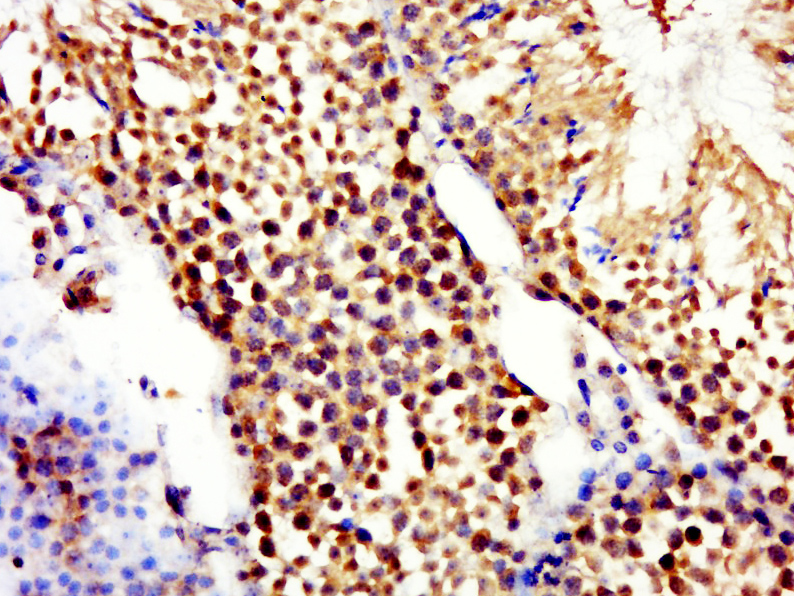

| 英文名称 | RNF16 Rabbit pAb |

| 产品应用 | IHC-P=1:100-500, IHC-F=1:100-500, IF=1:100-500 Not yet tested in other applications. |

| 交叉反应 | Mouse (Rat) |

| 免疫原 | KLH conjugated synthetic peptide derived from mouse TRIM17/RNF16 |

| {IHC-P} | {1:100-500} |

| {IHC-F} | {1:100-500} |

| {IF} | {1:100-500} |